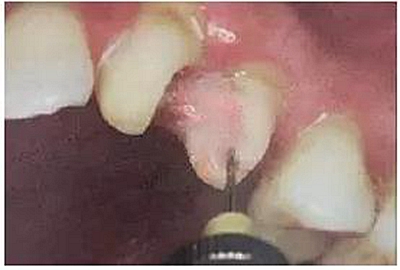

2. 清除根管壁殘留物

根管壁殘留物的存在直接影響纖維樁的粘接和固位,這也是導致纖維樁脫落的主要原因。

(根管內殘留物)

個人見解:必要的情況下先開闊根管口建立一定的視角后,慢速手機上G鉆為引導鉆,由號遞增引導開闊通路;P鉆預備樁道,同樣需要由小向大號遞增,直到選擇好適合的號預備到規(guī)定測量的深度即可,再配合纖維樁系統(tǒng)中各型號纖維樁所匹配的樁道

鉆,預備、修整成與纖維樁相適應的樁道。

預備后根管壁上會不同程度的牙膠和封閉劑等殘留物,所以樁道預備前后建議X線片輔助檢查預備深度等情況,而殘留物也會很清晰地顯現。

根管銼去除殘留物,很難去除干凈,而備取樁道時,禁止使用牙膠溶解劑(如:丁克除、氯仿)等有機溶劑去除殘留物,以防破壞根尖區(qū)牙膠的封閉和防止附著根管壁影響粘接。(超聲去除根管殘留物)

通常此時以超聲潔牙機更換較細工作尖進入根管(根管消毒沖洗液配合清潔工作后面會提到),徹底去除樁道根管壁上的附著殘留物,效果明顯。再配合X線片、根管顯微鏡輔助檢查清理的情況下更佳。